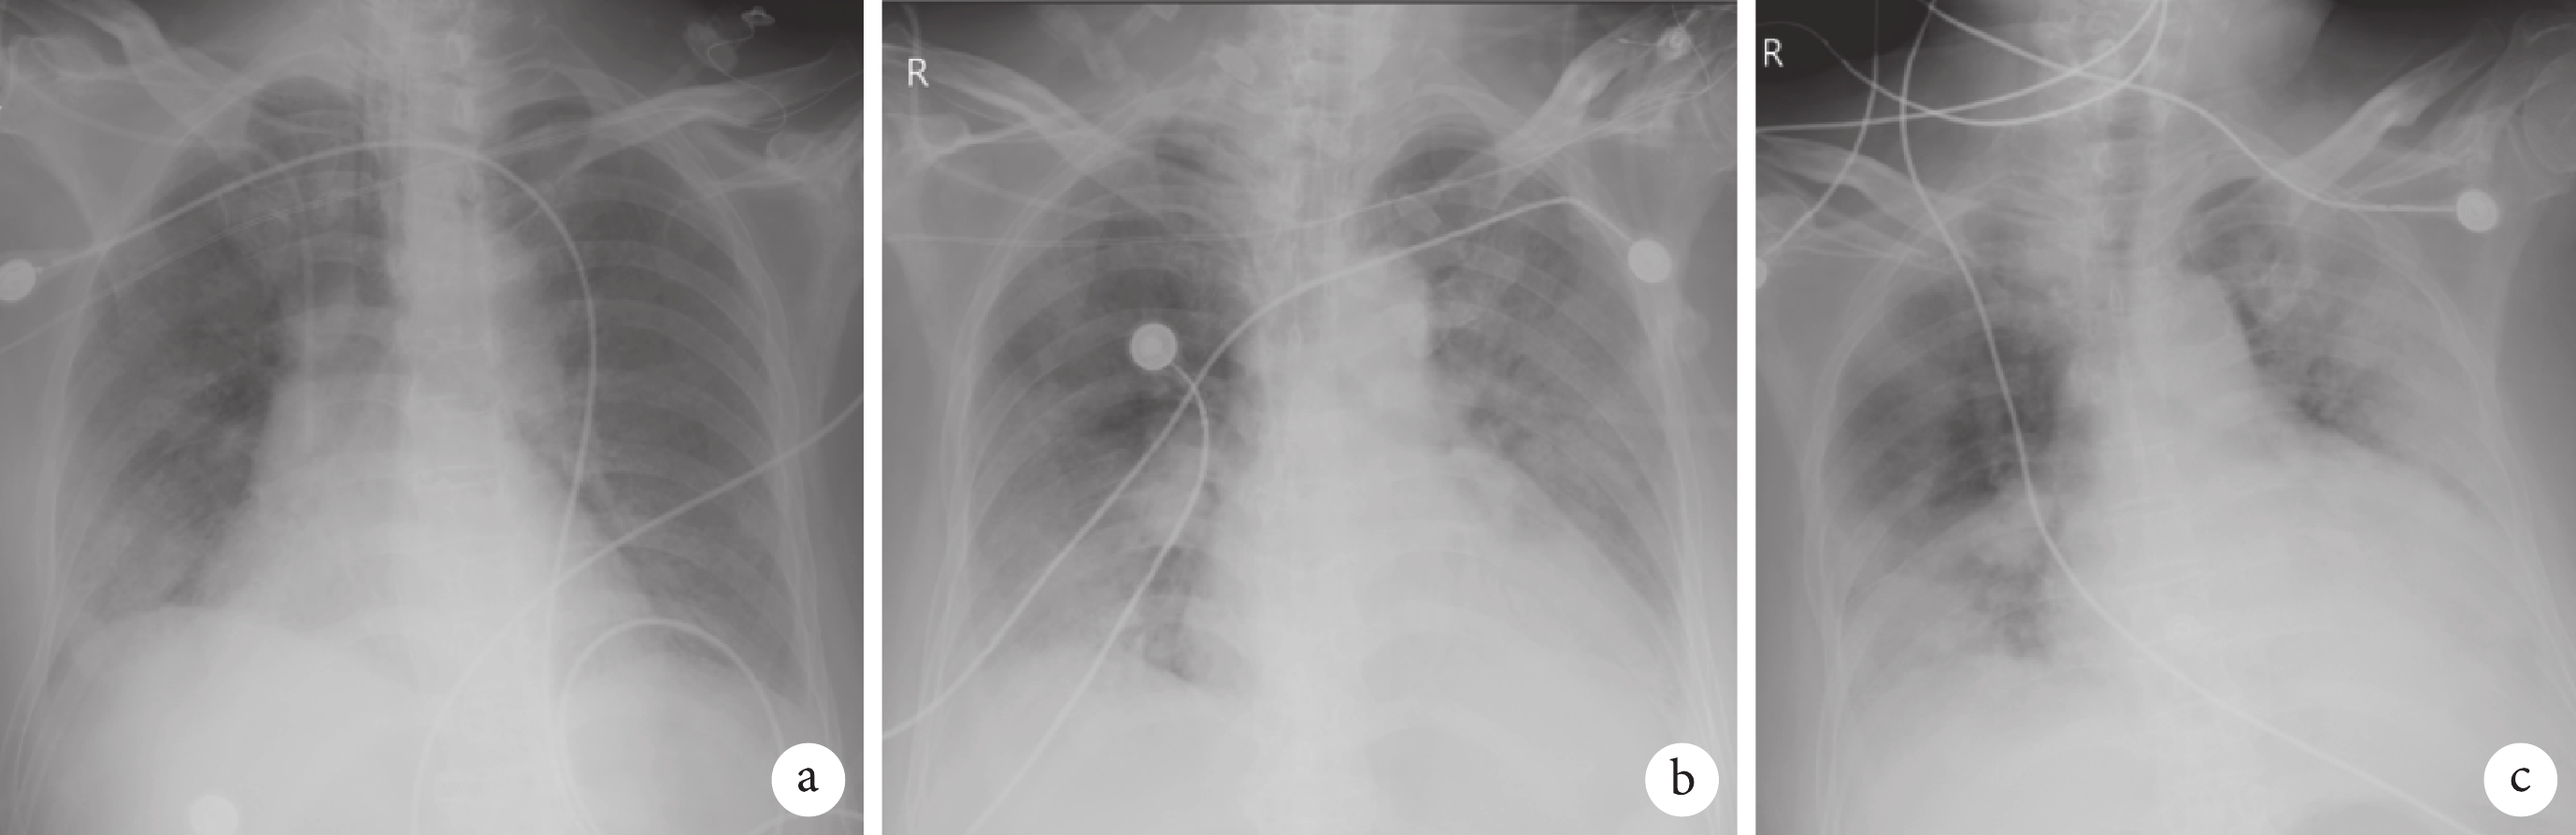

COVID-19 發病初期胸部影像學檢查 X 線片以多發小斑片影及間質改變為主(圖 1a),CT 則以肺外散在磨玻璃樣密度影為主(圖 1b);患者病灶可迅速增加,CT 顯示雙肺多發磨玻璃樣密度影,嚴重者向實變影轉變,可累及多個肺葉(圖 1c、1d)。本組病例中有 3 例出現呼吸衰竭、重癥肺炎,予有創機械通氣治療,床旁 X 線片顯示雙肺呈廣泛浸潤、實變,少數呈“白肺”改變(圖 2~4)。

a. 病程第 3 天;b. 病程第 8 天;c. 病程第 13 天。患者,男,81 歲,無創通氣 5 d 后轉有創通氣,病程早期雙肺散在小斑片影,病程后期雙肺呈廣泛浸潤、實變,呈“白肺”改變